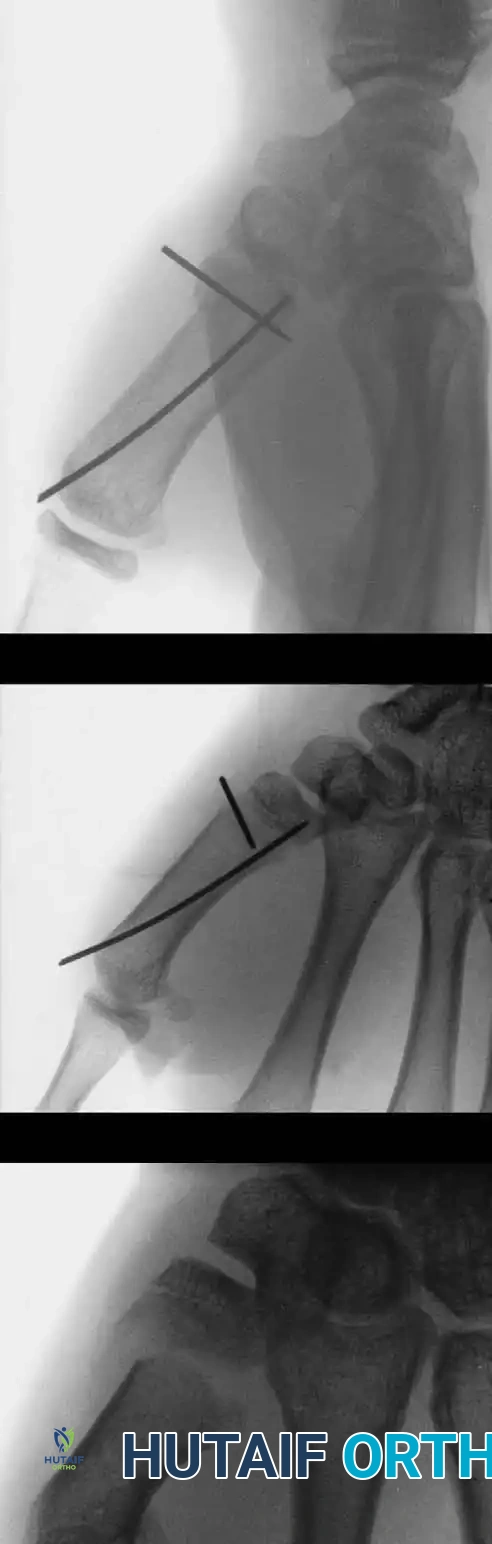

Image

Percutaneous Pinning Technique:

1. The short distal fracture fragment is clinically aligned with the middle phalanx by gentle hyperextension of the proximal interphalangeal (PIP) joint.

2. A K-wire is aligned clinically with the middle phalanx on the lateral side and drilled into the distal fragment.

3. A second K-wire is inserted on the contralateral side at a 45-degree angle to the proximal phalanx.

4. With both K-wires secured in the distal fragment, the fracture is reduced by bringing the PIP joint into slight flexion.

5. The wires are then advanced across the fracture site to emerge at the mid-diaphysis of the proximal segment, ensuring rigid, crossed-wire stability.